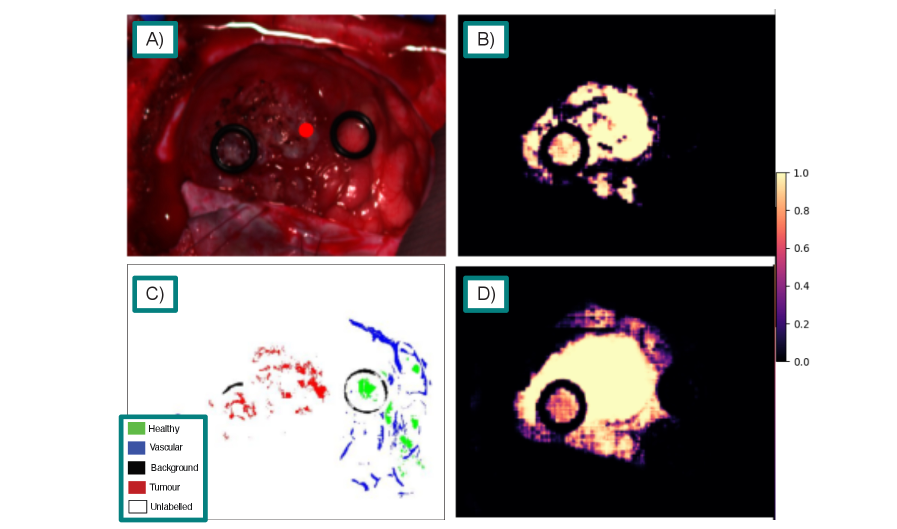

Qualitative comparisons further highlight the advantages of SAMSA2 over fine-tuned RGB baselines. On the HIB dataset (fig. 2), both SAMSA2-Large and SAM2-Large-FT correctly localise the tumour, but SAMSA2 provides a more refined boundary, offering greater clinical interpretability. On the SB-X and SB-H datasets (figs. 3 and 4), both methods capture the tumour within the marked region, yet SAMSA2 extends its prediction beyond the visible margins, suggesting the potential to reveal subsurface infiltration that may not be apparent in RGB-based predictions alone. For the HEIPOR dataset (fig. 5), performance is broadly comparable, though SAMSA2 produces fewer false positives, avoiding spurious activations in neighbouring tissue seen with SAM2-Large-FT. Finally, fig. 6 illustrates a representative workflow with SAMSA2-Large: tumour prompts reveal infiltration extending beyond the visible tumour boundary, while healthy prompts delineate the transition from normal to abnormal tissue. This bidirectional prompting demonstrates how SAMSA2 could support decision-making by helping identify resection margins more precisely.

Figure 3: Sample segmentation results on the SB-X dataset, tumour class. A) Pseudo-RGB image of the target. B) SAMSA2-Large standard predicted similarity. C) Ground truth labels. D) SAM2-Large-FT using SAM2 predicted similarity

Refer to caption